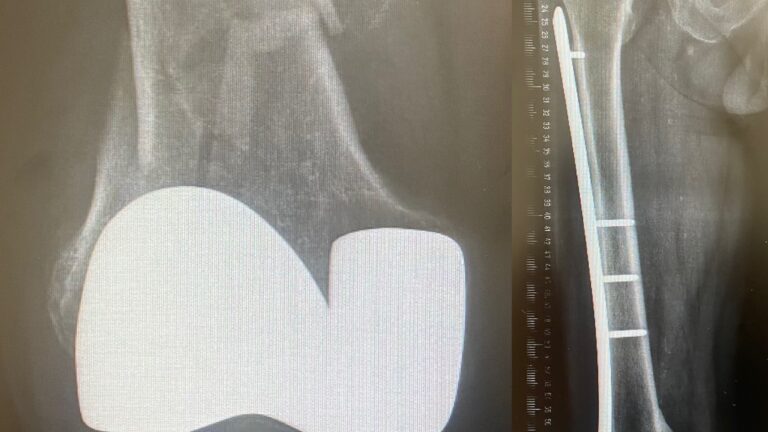

Säärimurtuma

Ennen – jälkeen